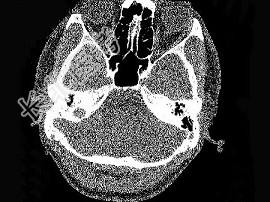

- 单项选择题男,23岁,右耳流脓十余年,右外耳道流脓,鼓膜穿孔,CT检查如图,最可能诊断为 ( )